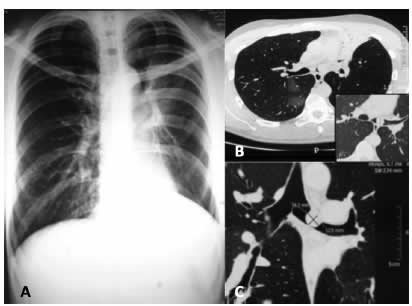

Al examen físico presentaba disminución de los ruidos respiratorios y de las vibraciones vocales asociados a sibilancias en el hemi-tórax izquierdo. En la radiografía de tórax se observó una pérdida de volumen a nivel del campo pulmonar superior izquierdo (Figura 1A). La TAC reveló una atelectasia del lóbulo superior izquierdo y una imagen de aspecto polipoideo de 16mm localizada en el bronquio fuente izquierdo (Figura 1B-C).